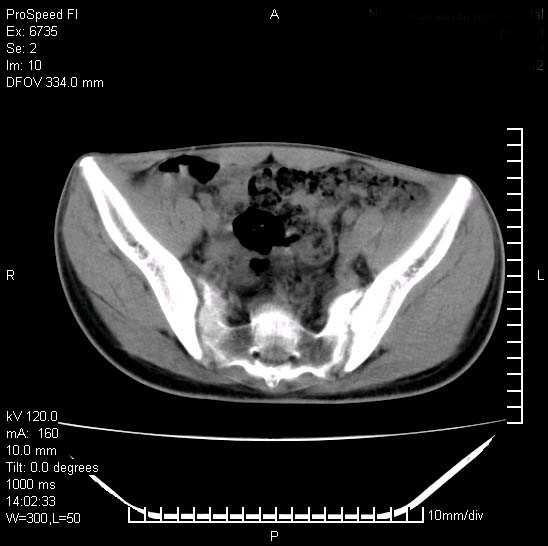

患者自诉胯部疼痛两年余,在当地服用中药,半月前至本院考虑骶髂关节结核,给予抗痨治疗。现发展至右下肢疼痛明显,活动受限,以膝关节处明显,拍膝关节平片无明显异常。

两侧骶骼关节改变,考虑强直性脊炎

左侧骶髂关节面限局性骨破坏,边缘硬化关节腔见钙化物;不出外tb

考虑强直性脊炎,建议查hla-b27

右侧骶髂关节也有类似改变,只是较左侧轻,首先考虑强直性脊柱炎,不除外结核,建议作hla-b27检查。

典型强脊炎改变,髋关节亦有累及

符合强直性脊柱炎表现。